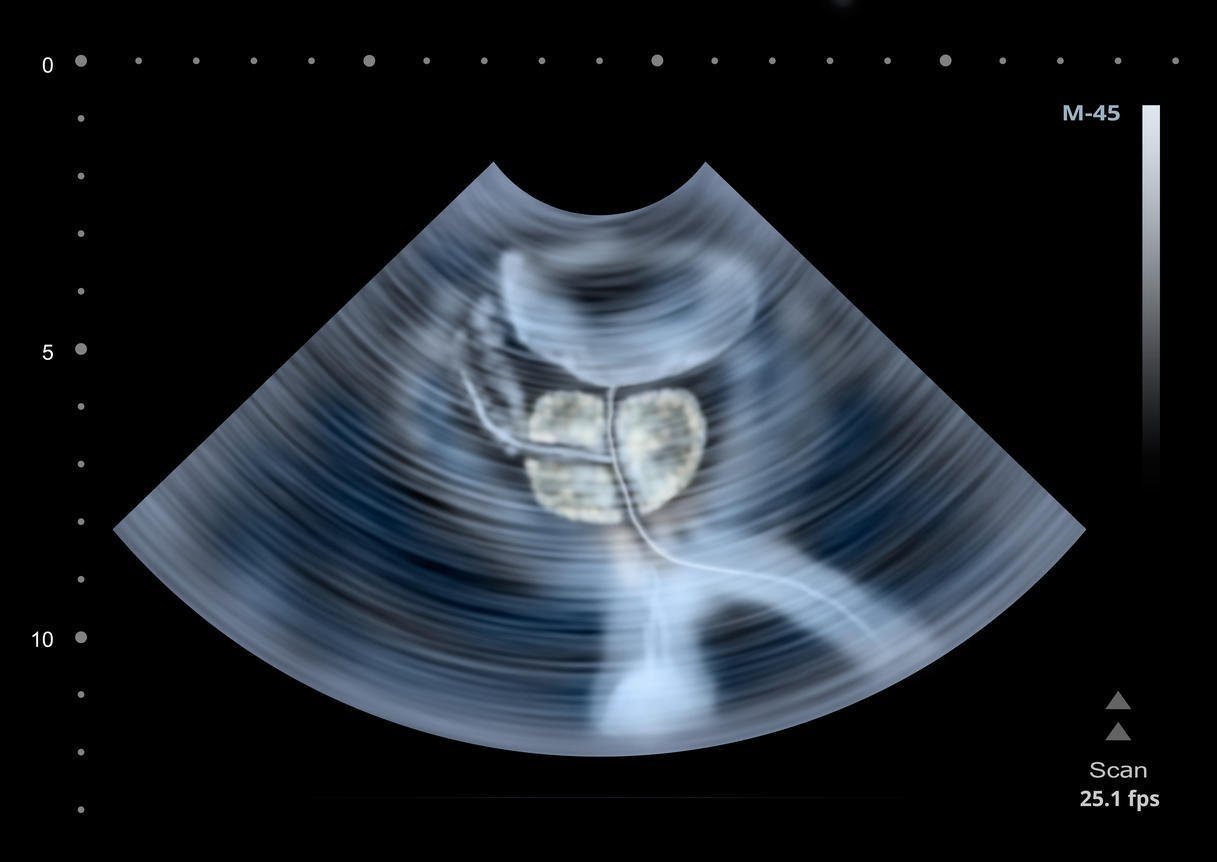

échographie de l'illustration de la prostate humaine

Istock

La prostate est une sorte de petite châtaigne située juste sous la vessie et qui entoure l’urètre, le canal par lequel sont évacuées les urines. Chez l’homme adulte, elle pèse entre 15 et 20 g. Lorsque le toucher rectal révèle une hypertrophie prostatique, l’urologue réalise une échographie accompagnée d’une exploration par voie endorectale. Ces examens permettent de calculer le volume de la prostate et d’étudier ses contours. Ils sont accompagnés d’une prise de sang. Les analyses sanguines visent, quant à elles, à établir le taux de PSA (antigène prostatique spécifique), une hormone sécrétée par la prostate. Un taux anormalement élevé de PSA peut être un signe d’adénome, de cancer de la prostate ou d’infection urinaire.